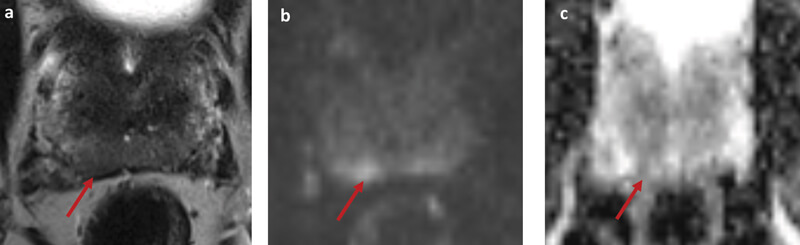

Figure 1: Example case; a ‘prostagram’ in a 57-year-old with PSA 1.02. He had no risk factors for prostate cancer and a benign DRE. A biparametric MRI (bpMRI) showed a basal right peripheral zone lesion with restricted diffusion on DWI (b) and corresponding hypointense signal on ADC (c). The lesion was score 4 out of 5 on PIRADS v2 and LIKERT scales. A targeted biopsy revealed Gleason 3+4 in all targeted cores with maximum cancer core length 7mm.

There are individual cases of MRI detecting significant disease in men with a low PSA and normal DRE (Figure 1). At present there have been limited studies evaluating MRI as a replacement for PSA. A small pilot study of MRI screening in 47 healthy volunteers has been completed by Nam et al. [8]. Although the sample size was small, the ROC curves suggested that MRI might have a higher diagnostic accuracy compared to PSA.